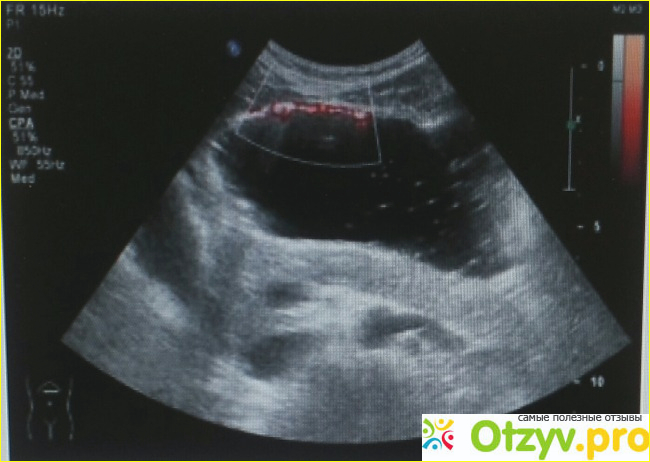

Ультразвуковое исследование (УЗИ), сонография - это неинвазивное исследование организма человека или животного с помощью ультразвуковых волн.

Делают УЗИ для полной постановки диагноза. Оно может использоваться как основной способ диагностики, так и для уточнения заболевания. УЗИ помогает обнаружить скопление газа или жидкости в брюшной полости. Это для человека наиболее приятное обследование. Просто нужно придти натощак и полежать на кушетке, «грубо говоря».